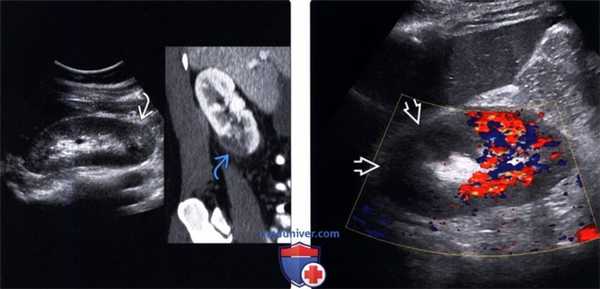

(Слева) УЗИ в режиме серой шкалы: у женщины с трансплантированной почкой выявлена клиновидная область пониженной эхогенности верхнего полюса трансплантата.

(Справа) На соответствующем цветовом допплеровском исследовании у этой же пациентки выявлено отсутствие кровотока в пределах верхнего полюса. Инфаркты часто плохо выявляют в режиме серой шкалы. (Слева) На изображении артериального В-потока выявлен участок предполагаемого инфаркта.

(Справа) Недостаток кровоснабжения наиболее очевиден на данном изображении венозного В-потока. Пациенту в тот же день была выполнена биопсия почки, на которой была выявлена обширная область инфаркта, предположительно вследствие васкулита или хронического отторжения. (Слева) УЗИ в режиме серой шкалы: у женщины 60 лет с трансплантацией почки и поджелудочной железы в анамнезе, а также жалобами на боль в нижней части живота выявлен сниженный внутрипочечный кровоток. Обратите внимание на небольшое расширение собирательной системы.

(Справа) КТ, аксиальная проекция: у этой же пациентки выявлены значительное увеличение и смещение трансплантированной почки (почка была пересажена в нижний левый квадрант). Пациентке проведено экстренное хирургическое вмешательство, при котором был обнаружен перекрут интраперитонеального трансплантата.

(Левый) У пациента с дилатационной кардиомиопатией в нижнем полюсе правой почки при УЗИ визуализируется слабо выраженный клиновидный гиперэхо генный инфаркт. На соответствующем КТ срезе с контрастированием визуализируется дефект контрастирования в этой области. Обратите внимание на неизмененное контрастирование капсулы (симптом «кортикального края»), обусловленное интактностью капсулярных артерий, кровоснабжающих капсулу.

(Правый) При цветовой допплерографии в верхнем полюсе почки у пациента с сегментарным инфарктом почки кровоток не визуализируется.